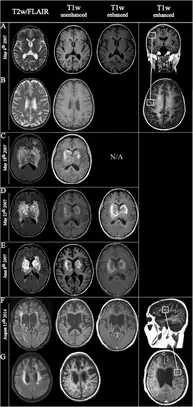

Fulminating ADEM showing many lesions. The patient survived, but remained in a persistent vegetative state

ADEM produces multiple inflammatory lesions in the brain and spinal cord, particularly in the white matter. Usually these are found in the subcortical and central white matter and cortical gray-white junction of both cerebral hemispheres, cerebellum, brainstem, and spinal cord,[16] but periventricular white matter and gray matter of the cortex, thalami and basal ganglia may also be involved.